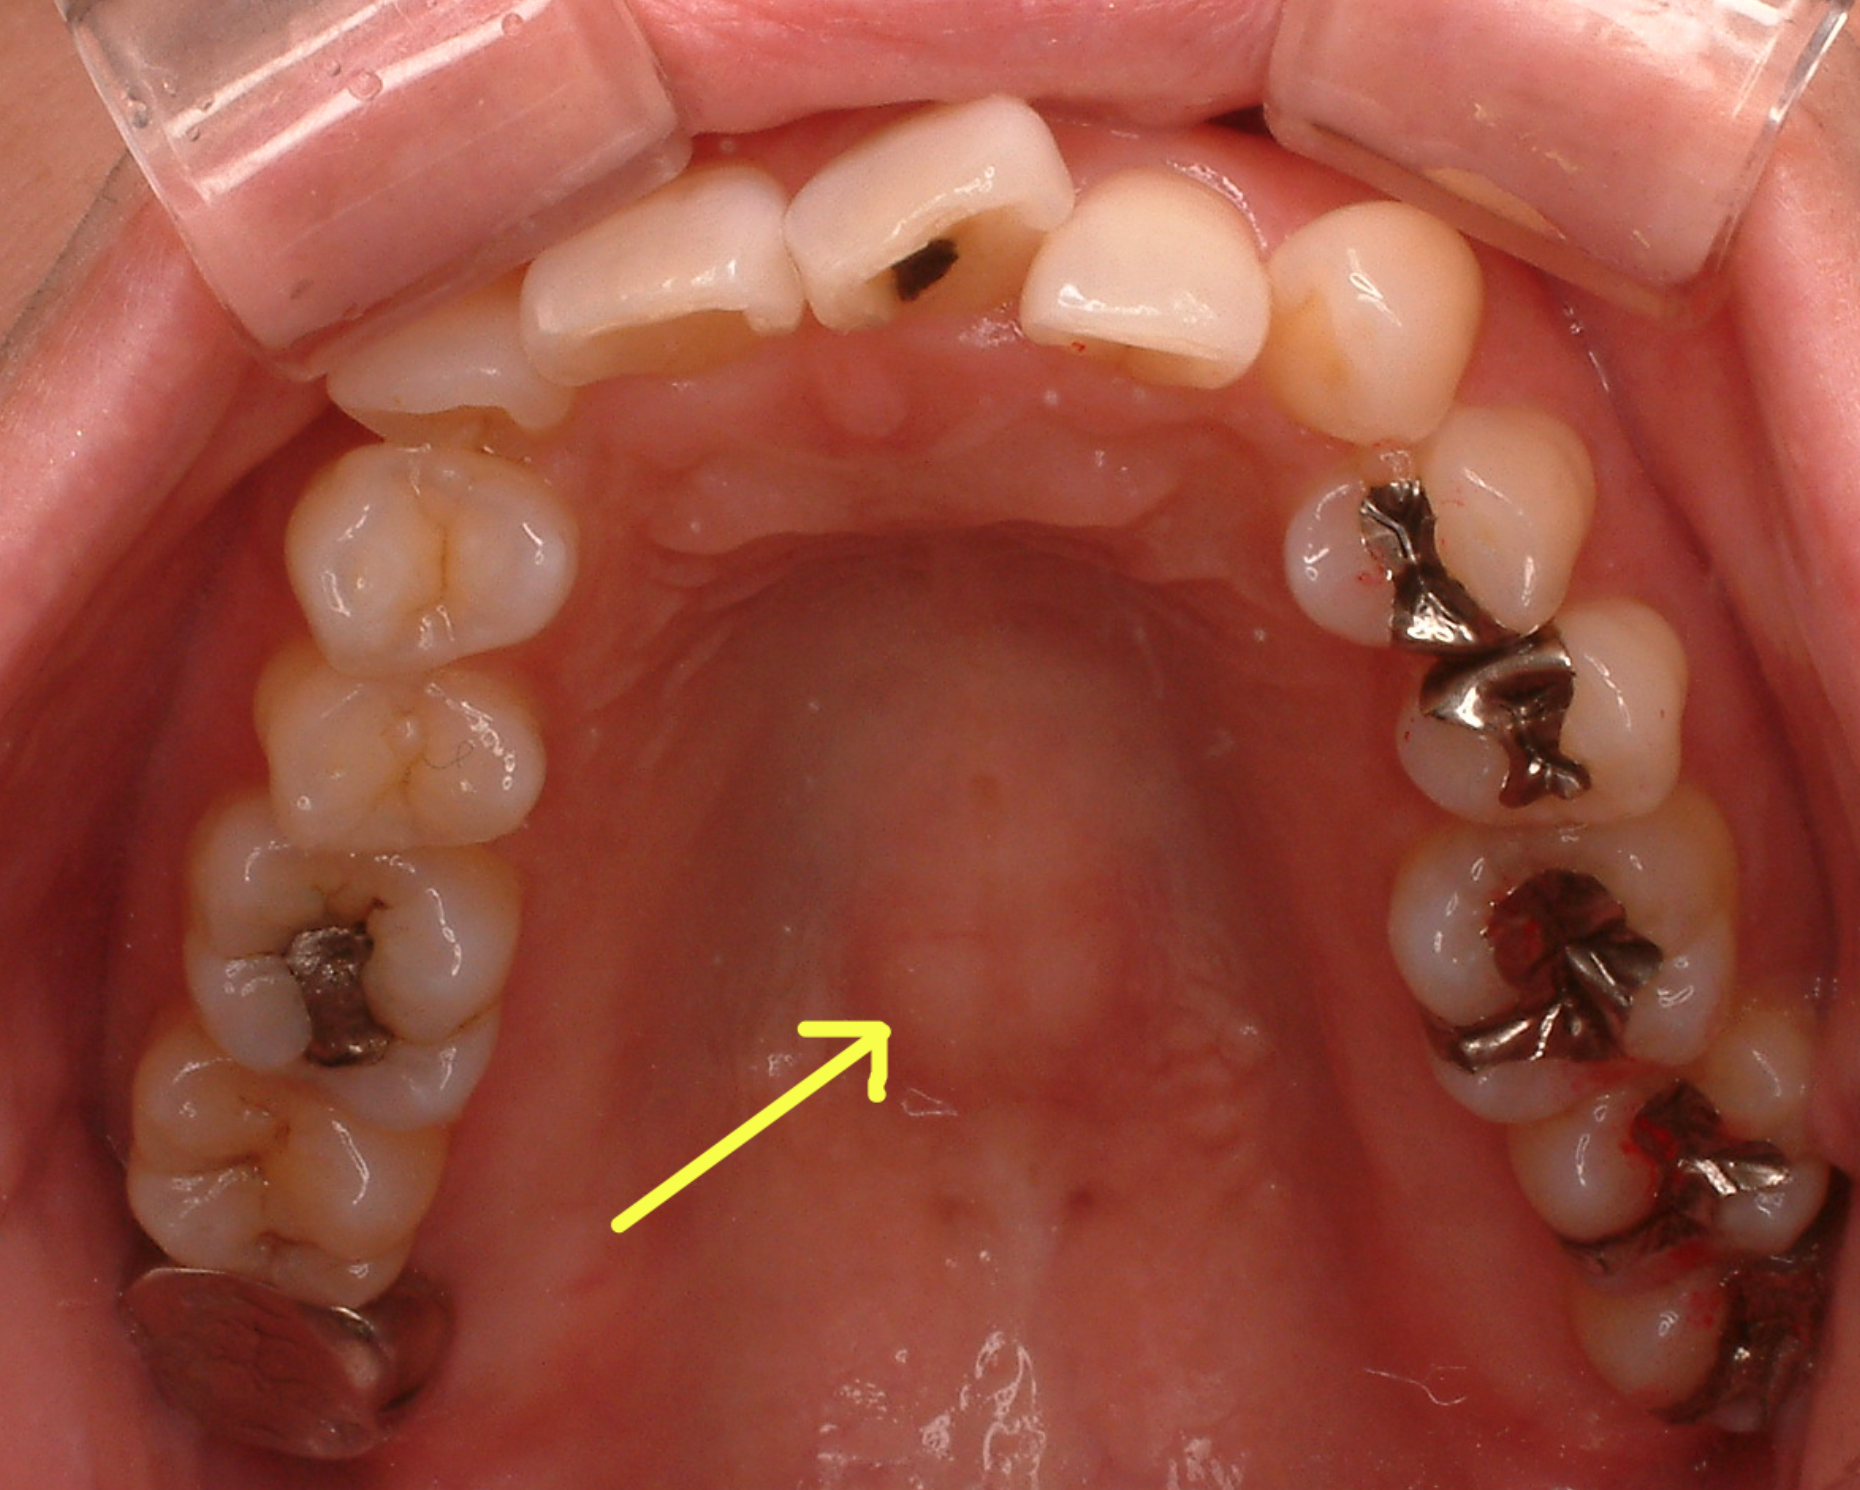

その他骨のところに現れるサインでは、上の顎の内側の真ん中が盛り上がってくることもあります。

その他、頬っぺたの内側に白い線がです。下の脇がデコボコしている等も噛み締めの習慣があるサインです。